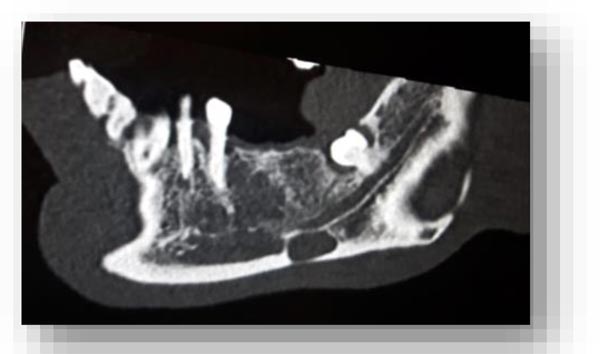

In this radiographic exam, we found an oval notch with radiolucent, clear and regular borders, located in the inferior portion of the horizontal branch of the mandible, on the lingual side, near the angle of the mandible, and below the mandibular canal. The X-ray allowed precise measurement showing a height ranging between 13.5 mm and 17 mm and breadth between 6 and 8 mm (Figs. 4-5).

The bi-dimensional reconstructions in parasagittal slices also permitted better identification of the closeness of the bone cavity to the canal of the alveolar inferior omolateral nerve, whereas the computerized volume rendering offered a more accurate view of the surrounding anatomical features (Figs. 6-12).